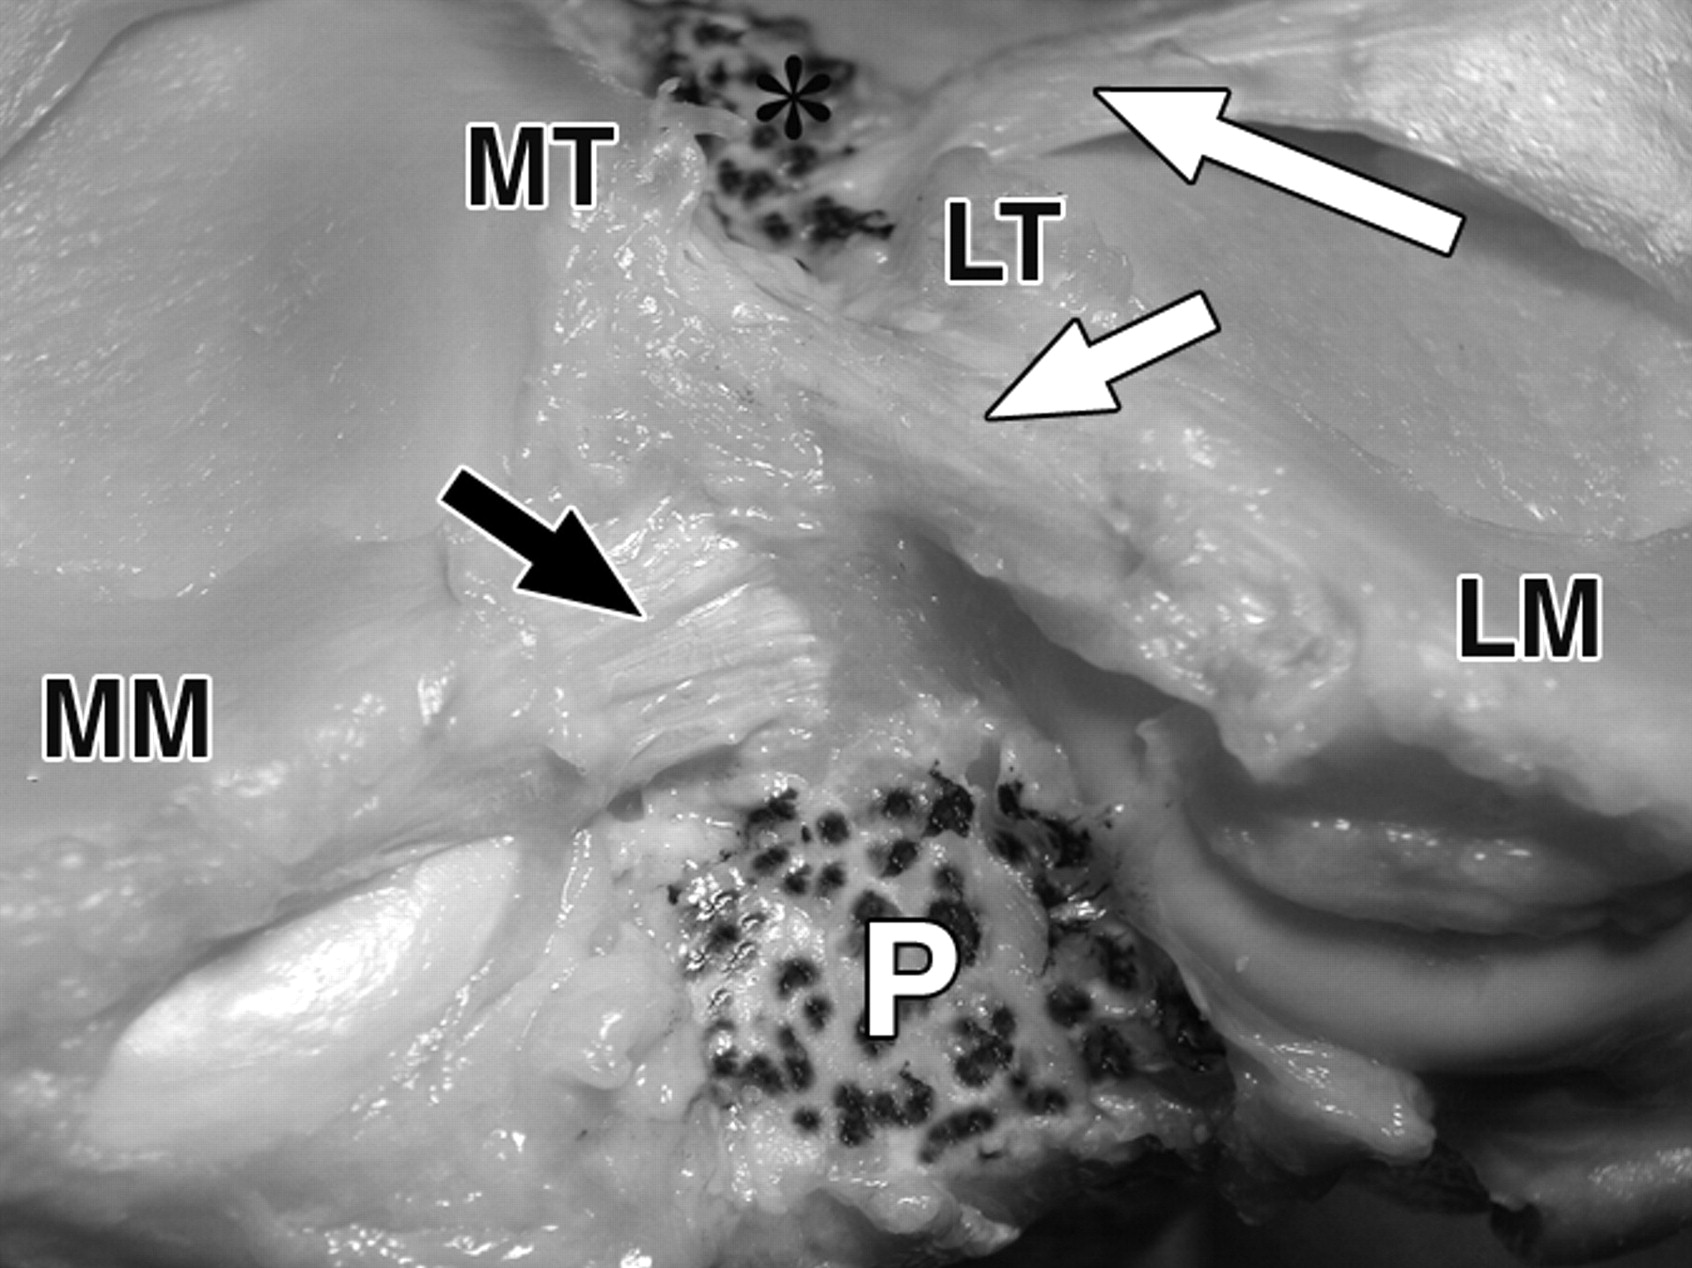

图1C-59岁男性。

黑色长箭头表示内侧半月板(MM)前根;黑色短箭头表示内侧半月板后根;白色长箭头表示外侧半月板(LM)前根;白色短箭头表示外侧半月板后根。侧视图显示了去除软组织结构后胫骨插入部位的相对位置。星号表示前十字韧带。P =后交叉韧带。

图1D-59岁男性大体标本。

黑色长箭头表示内侧半月板(MM)前根;黑色短箭头表示内侧半月板后根;白色长箭头表示外侧半月板(LM)前根;白色短箭头表示外侧半月板后根。照片对应于C。MP =内侧胫骨平台,MT =内侧胫骨结节,LT =外侧胫骨结节,LP =外侧胫骨平台。P =后交叉韧带。

图4A-59岁男性大体标本。

照片显示了前、后交叉韧带胫骨止点的解剖关系。

胫骨平台的后视图,去除了韧带和韧带,显示了外侧半月板后根(白色箭头)、内侧半月板后根(黑色箭头)和后交叉韧带(P)的附着点轮廓。MP =内侧胫骨平台,MT =内侧胫骨结节,LT =外侧胫骨结节,LP =外侧胫骨平台。

图4C-59岁男性大体标本。

去除交叉韧带后的膝关节后视图对应于B。长白色箭头表示外侧半月板(LM)的前根。短白色箭头=外侧半月板后根,黑色箭头=内侧半月板后根(MM),MT =内侧胫骨结节,LT =外侧胫骨结节,P =后交叉韧带。